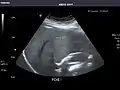

Gallbladder

Gallbladder: No stones, wall thickening, or pericholecystic fluid.

Common Bile Duct: Nondilated measuring 1.3 mm at the level of the porta hepatis.